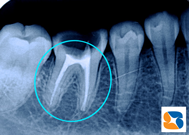

神経を抜いた後に薬を詰める

コラム「神経を抜いた後に薬を詰める」の画像